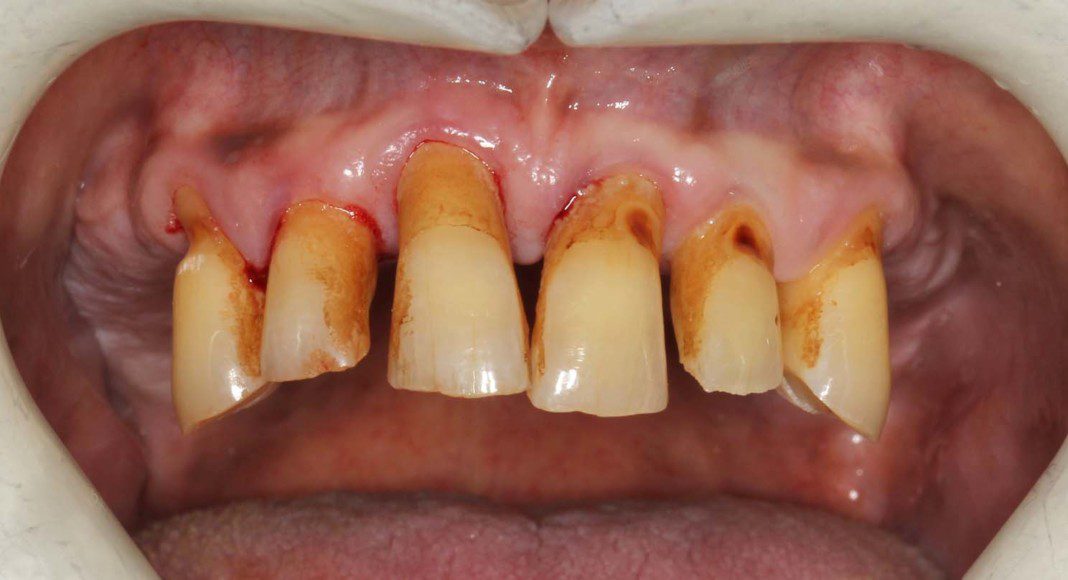

Through a process of acrylic addition and subtraction, upper and lower temporary bridges are fabricated. Both upper and lower temporary bridges are placed for use until the back implants are placed and ready to restore. This patient has a serious grinding habit. He grinds and abuses his teeth all day. The grinding sound can be heard when he is in the office. These bridges were made of a very hard acrylic resin and all the same piece of acrylic unlike All-0n-4 temporaries which are converted dentures and much weaker. In spite of our best efforts, he was able to break these temporaries on a regular basis.

Same temporary bridges after four months… stained, broken, and battered. We kept him going while the upper back bone grafts were healing.